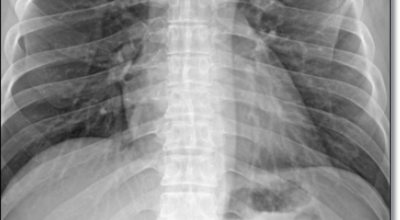

일반인이 근육통과 금이 간 경우의 차이는 거의 판별하기 힘들어요. 갈비뼈라고 하는 부분이 눈에 보이도록 붓는 것도 아니고, 멍이 들어서 아픈것도 아니기 때문이지요. 가장 정확하게 판별하는 방법은 엑스레이를 찍는 방법이지요.